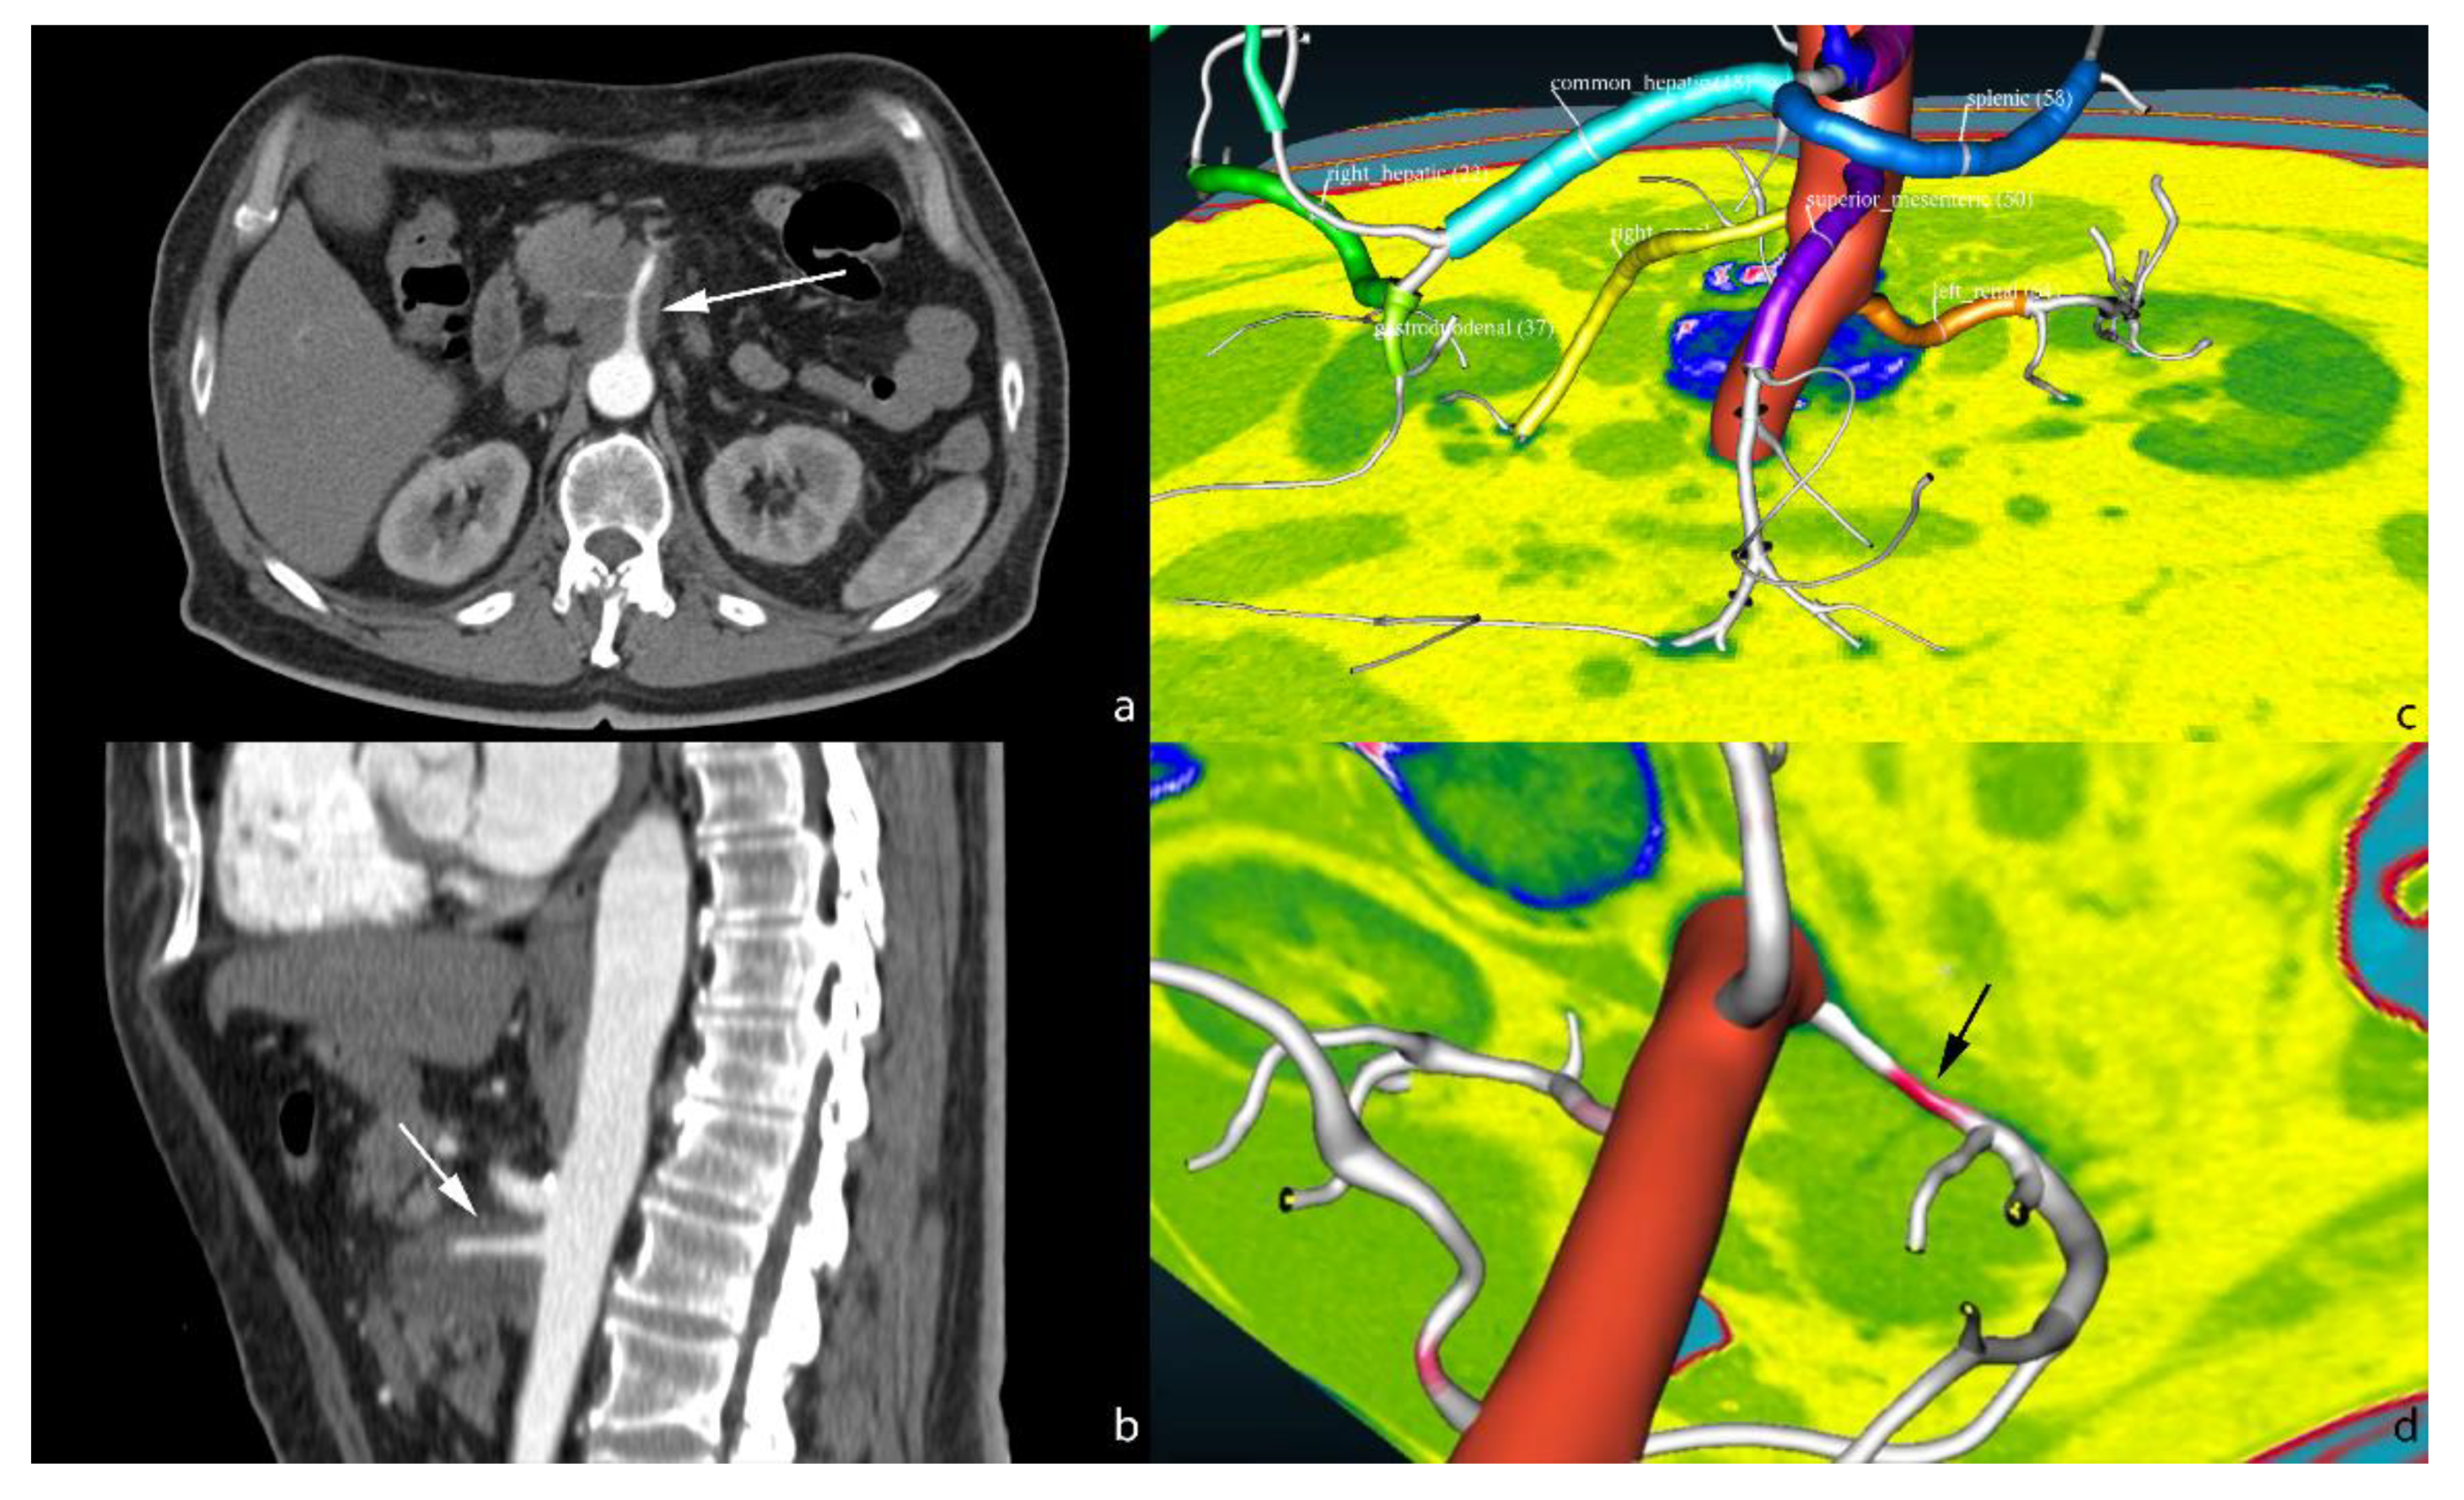

2. Segmentation

- Fabiano, F.; Dal, P. An asp approach for arteries classification in CT-scans? CEUR Workshop Proc. 2020, 2710, 312–326. [Google Scholar]